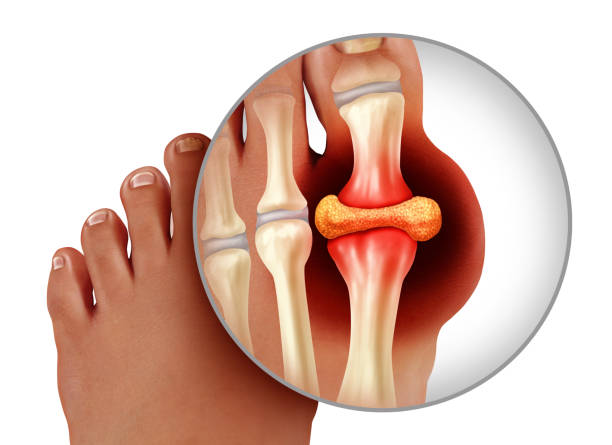

통풍 치료는 그 발병원인에 따라 치료방법이 달라지는데 반복해서 재발, 과거 가족력, 요로 결석 치료 이력, 콩팥 기능에 따라 치료 방향이 달라진다고 합니다. 통상적 치료는 통풍 주요 원인인 요산 수치를 떨어뜨리는데에서 시작하는데 요산 생성을 억제 혹은 요산 배출을 늘리는 식으로 요산 수치를 떨어뜨리는데 집중하는데 사실 이렇다하더라도 재발 가능성이 있어 고혈압과 같이 대사질환으로 관리해야 합니다.

따라서 요산수치를 내려 치료를 잘 받더라도 생활습관을 개선하지 않으면 재발가능성이 높아 금주는 물론, 소고기, 돼지고기 등의 붉은고기류, 조개, 어패, 새우류의 단백질 섭취, 탄산음료 및 맥주음료 등의 식단을 피하는 것이 중요합니다.